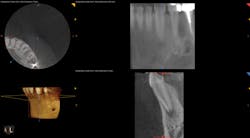

To determine whether tooth No. 21 or No. 22 was the issue, two periapical radiographs were taken. However, the results were inconclusive (figures 2–4). With clinical testing and 2-D radiographs providing no smoking gun, it was decided to use limited field-of-view CBCT (Carestream Dental CS 9000C 3D) on the region. CBCT revealed that tooth No. 22 was abscessed and a fair amount of the apical bone was completely gone (figures 5 and 6). In fact, since the time the pain began and when the patient presented at the practice, the tooth had abscessed at an alarming rate and was now considered an emergency situation.

Figure 6: CBCT showing a single view of the periapical lesion in the lower right of the screenshot